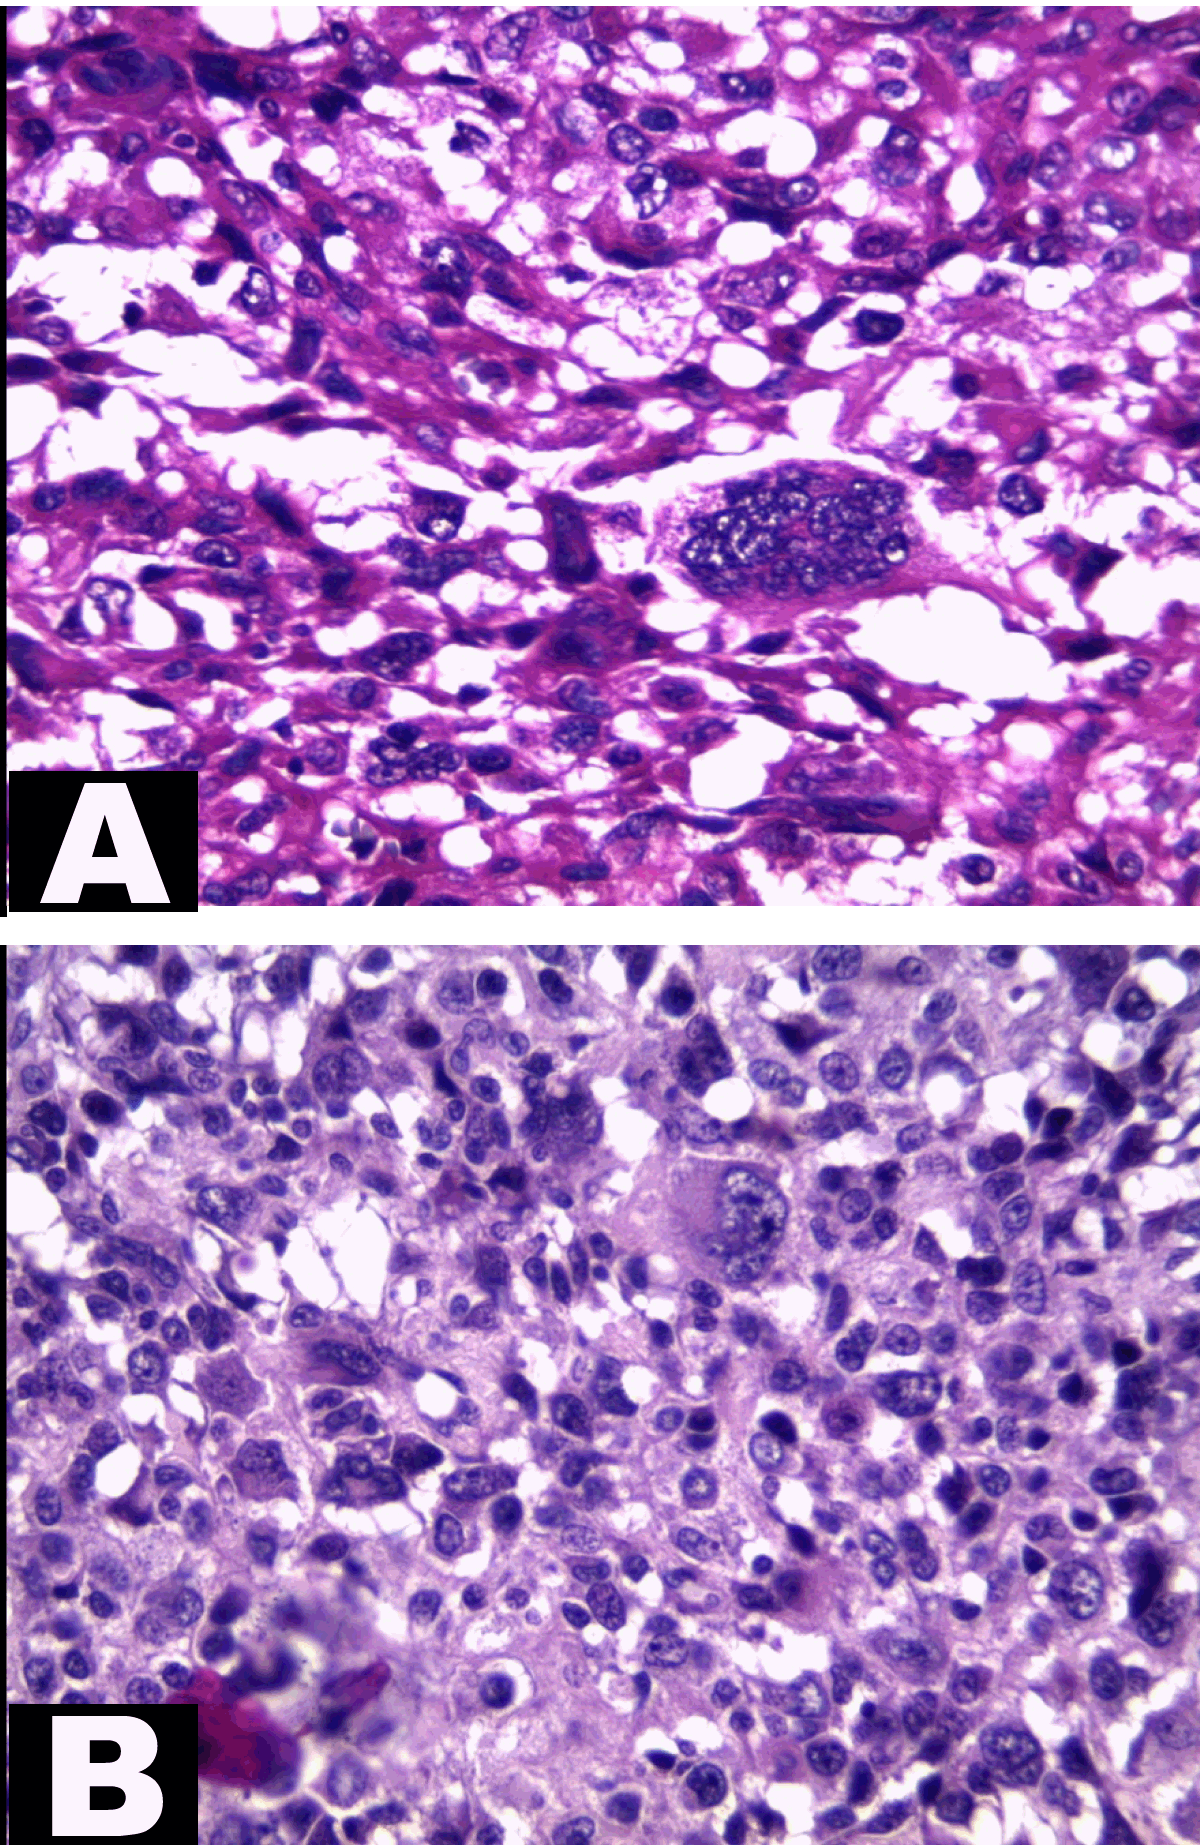

At the pathology laboratory, we received a piece of the left lower limb amputation. (Figure 2) We opened it. Gross examination of the resected distal femur revealed a 22x5 cm intramedullary multicystic hemorrhagic destructive tumor with cortical destruction and extension into the adjacent anterior and posterior soft tissues. The latter component of the mass was larger than the intraosseous tumor. (Figure 3) The articular surface was not involved. We cut the femur in its longest axis with electric saw. (Figure 4) Fixation in 10% neutral buffered formalin for 48 hours and decalcification of bone with nitric acid were performed. Slice of bone section was included in full. Many specimens from soft tissues and the surgical margins were also taken. Microscopic view of histological specimens of tumor stained with hematoxylin andeosin showed prominent blood filled cysts with malignant stroma in septa separating cysts. (Figure 5) (Figure 6) It contained atypical tumor cells oval or round of variable size with osteoblast-like multinucleated giant cells and a variable amount of immature osteoid. (Figure 7) (Figure 8) (Figure 9) (Figure 10) (Figure 11) (Figure 12) Numerous mitotic figures were noted (Figure 13). The tumor was located at 6 cm from the bone limit and 2 cm at the edge of the soft tissues. The resection margins were negative. The marrow, scooped and submitted separately, was negative.

Figure 9: (A, B) High magnification showing nuclear pleomorphism of sarcomatous septal cells and tumor giant cells (H&E stain, x400).

Figure 10: Tumor osteoid in septum bordering blood-filled space. Higher magnification showing irregular, finely divided (lace-like) strands of osteoid (H&E stain, x400).

Microscopic findings revealed highly pleomorphic cells and foci of bone matrix formation between blood filled cyst like spaces, confirming the diagnosis of telangiectatic osteosarcoma. In some cases, where septa have broken down, atypical stromal cells may be identified, free-floating within the blood clot.[4] The amount of osteoid varies, but usually fine and lacelike osteoid is observed in minimal amount. [1] [4][6] However, this feature is not essential to establish the diagnosis of telangiectatic osteosarcoma. [4]